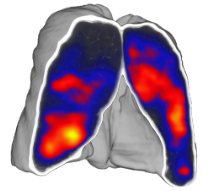

- Quantitative analysis of complex lung patterns and diseased regions

Post-treatment evaluation and response monitoring